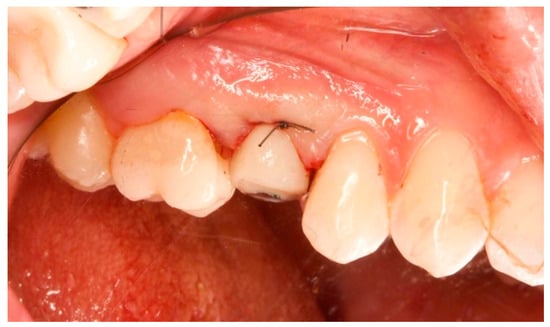

Figure 15.

One-year follow-up. Element 1.5.